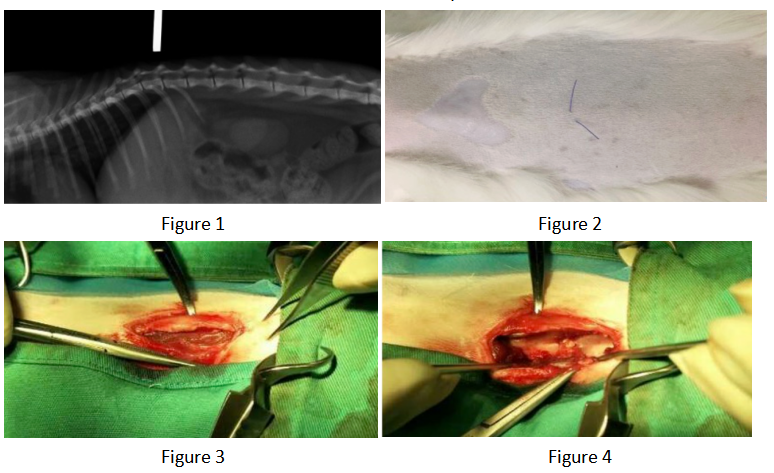

Figure 1 Preoperative CR image

The hemilaminectomy site was redefined preoperatively based on plain X-rays (Figures 1 and 2). Surgical approach: A single incision of the skin and subcutaneous fat was made parallel to the dorsal midline, offset 1 cm (Figure 3). The lumbar multifidus muscle attached to each spinous process was exposed using a scalpel. The lumbar multifidus muscle was then bluntly dissected from the lamina using a periosteal elevator until it reached the facet articular processes (Figure 4). One or two articular processes were dissected in sequence, anterior and posterior to the affected area, and the surrounding tissue was completely separated from the bone to fully expose the articular processes. A rongeur was used to create a bite mark in the lamina anterior and posterior to the affected area, with repeated manipulations to deepen the mark. When cancellous bone was visible (Figure 6) and the dura mater was visualized, the rongeur was discontinued and replaced with a nucleus pulposus forceps, carefully removing the bone from the lamina to expose the medullary cavity. The rongeur and nucleus pulposus forceps were then used alternately to remove the affected articular processes, further exposing the medullary cavity (Figures 7 and 8). After the main surgery, the wound is irrigated, blood clots and bone fragments are removed, a fat pad is placed on the exposed medullary cavity, the lumbar muscles are repositioned, and the dorsal fascia is sutured. The skin tissue is closed routinely.